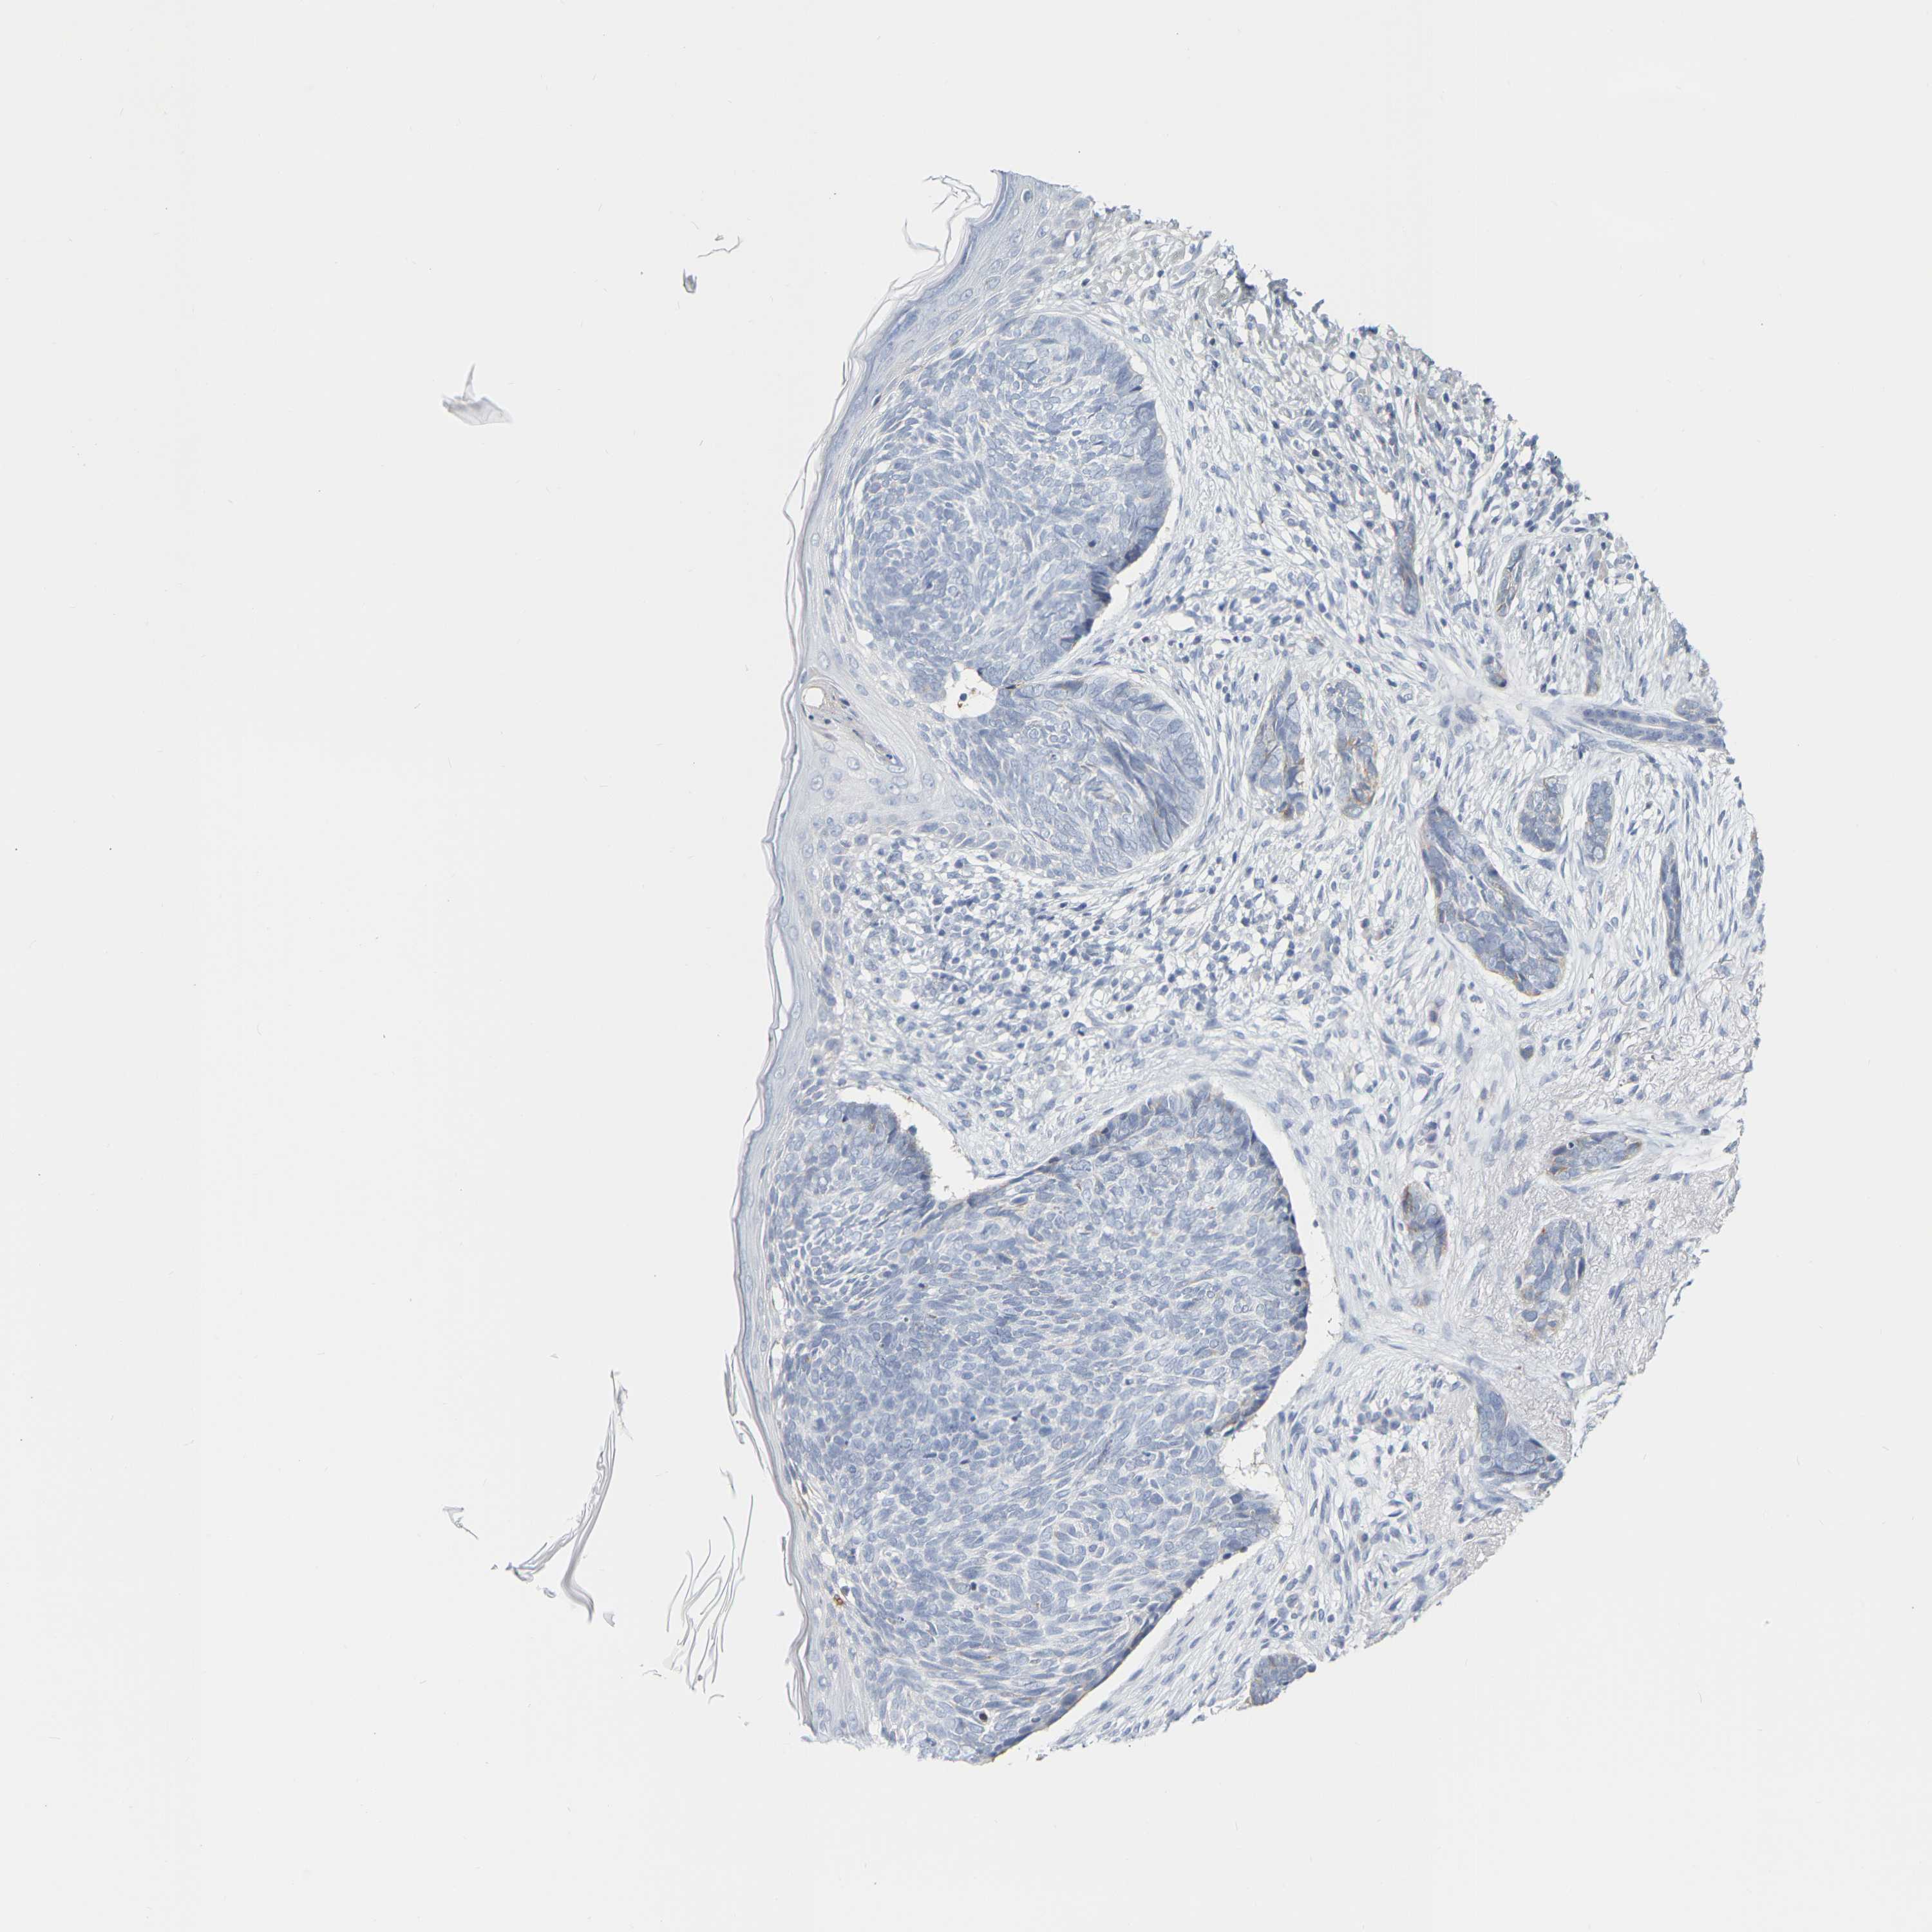

SKIN CANCER - Protein expressioni

A mouse-over function shows sample information and annotation data. Click on an image to view it in a full screen mode. Samples can be filtered based on level of antibody staining by selecting one or several of the following categories: high, medium, low and not detected. The assay and annotation is described here.

Each image is clickable and will lead to virtual microscopy that enables deeper exploration of all samples and also displays staining intensity scores, fraction scores and subcellular localization as well as patient and tissue information for each sample.

Antibody CAB010337

Staining

High

Medium

Low

Not detected

Intensity

Strong

Moderate

Weak

Negative

Quantity

>75%

75%-25%

<25%

None

Location

Nuclear

Cytoplasmic/membranous

Cytoplasmic/membranous,nuclear

Squamous cell carcinoma, NOS